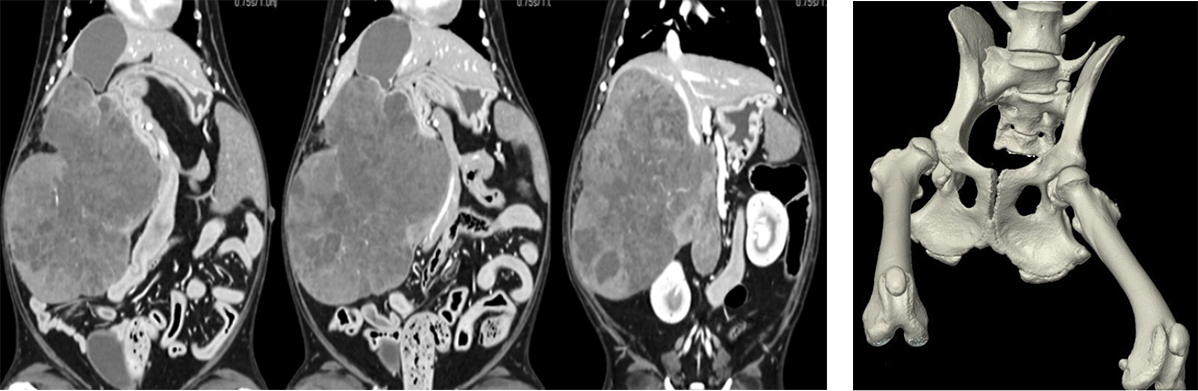

Àü»êÈ´ÜÃþÃÔ¿µÀåÄ¡(Computed Tomography>´Â X¼± ¹æ»ç¼±°ú ÄÄÇ»Å͸¦ Ȱ¿ëÇÏ¿©

¹Ý·Áµ¿¹°ÀÇ ½Åü ±¸Á¶¸¦ ´Ü¸é ¿µ»óÀ¸·Î ÃÔ¿µÇÏ¿© À̸¦ À籸¼ºÇÑ ÈÄ

xray³ª ÃÊÀ½ÆÄ¿¡¼ È®ÀÎÇÒ ¼ö ¾ø´Â ±¸Á¶¹°À̳ª ¿µ»ó±îÁö È®ÀÎÇÒ¼ö ÀÖ´Â »óÀ§±Þ ¿µ»óÁø´Ü ±â°èÀÔ´Ï´Ù.